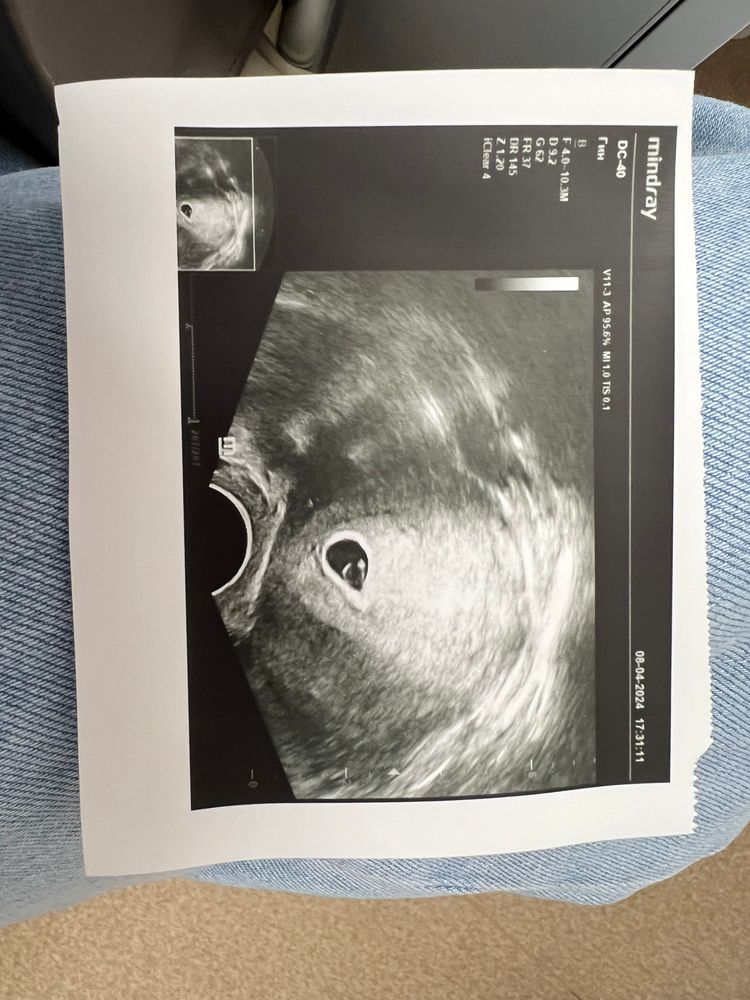

УЗИ 21дпп. Большое пя?

Не похоже по снимку что пя 20 мм,жм 4 мм на фоне половина пя занимает

Юля, написано,но по фото кажется меньше,судя по тому что жм 4 мм и на фоне пя занимает третью часть пя,то пя 12 мм кажется,а не 20 мм,может ошиблись с замерами,но на 21 дпп рано для эмбриона

Большое ПЯ - не маленькое) а эмбрион появится по сроку. На 21ДПП не у всех фиксируют эмбрион. У вас очень хороший ЖМ и вообще даже на фотке видно, что эмбрион уже прослеживается) сходите через 4-5 дней. Все увидите, возможно и послушаете даже)

У вас там виден намек на эмбрион. У меня на 6+3 недели появился (не помню какой это дпп). Надо было чуть попозже пойти))